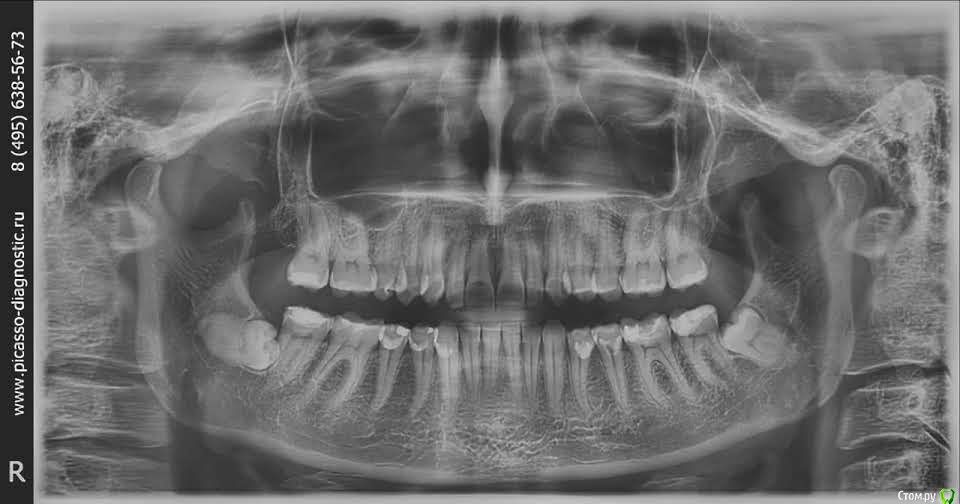

karlos1999 Опубликовано 14 января, 2019 Поделиться Опубликовано 14 января, 2019 День добрый! Всех с прошедшими праздниками!!! Подскажите пожалуйста, у меня обе нижние восьмерки (верхних вроде бы нет совсем) выросли в десне, на данный момент воспалений нет и меня они почти не беспокоят (может раз в год десна припухает, как будто зуб растет, но боль не сильная). Хотелось бы понять их лучше удалить сейчас или оставить все как есть и удалить, если начнутся осложнения. И существуют ли их при удалении какие нибудь серьезные риски, типа лицевого паралича, или неконтролируемого слюнотечения (я в этом плохо разбираюсь, по-этому, если глупость ляпнула-извиняюсь). Буду благодарна за ответы. Снимок прикрепляю. Спасибо. Ссылка на комментарий